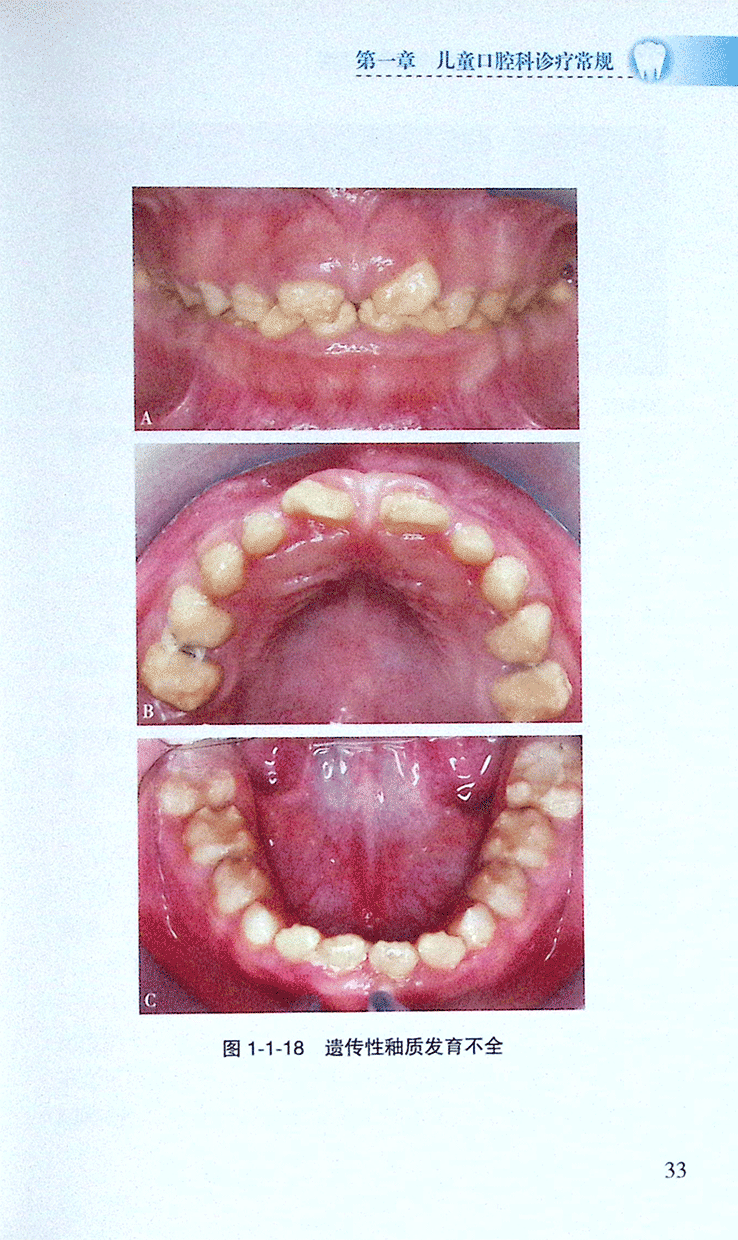

>>(一)釉质发育不全